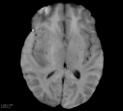

Deep neural network models used for medical image segmentation are large because they are trained with high-resolution three-dimensional (3D) images. Graphics processing units (GPUs) are widely used to accelerate the trainings. However, the memory on a GPU is not large enough to train the models. A popular approach to tackling this problem is patch-based method, which divides a large image into small patches and trains the models with these small patches. However, this method would degrade the segmentation quality if a target object spans multiple patches. In this paper, we propose a novel approach for 3D medical image segmentation that utilizes the data-swapping, which swaps out intermediate data from GPU memory to CPU memory to enlarge the effective GPU memory size, for training high-resolution 3D medical images without patching. We carefully tuned parameters in the data-swapping method to obtain the best training performance for 3D U-Net, a widely used deep neural network model for medical image segmentation. We applied our tuning to train 3D U-Net with full-size images of 192 x 192 x 192 voxels in brain tumor dataset. As a result, communication overhead, which is the most important issue, was reduced by 17.1%. Compared with the patch-based method for patches of 128 x 128 x 128 voxels, our training for full-size images achieved improvement on the mean Dice score by 4.48% and 5.32 % for detecting whole tumor sub-region and tumor core sub-region, respectively. The total training time was reduced from 164 hours to 47 hours, resulting in 3.53 times of acceleration.